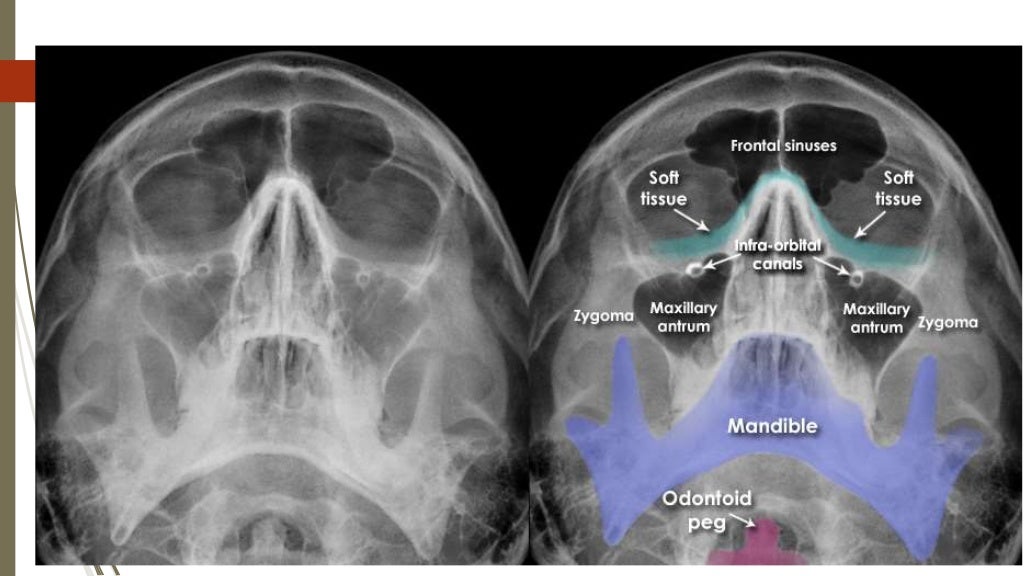

Facial Bones Om View . The zygomatic arch looks like an elephants trunk on. Pa 30° (modified parietocanthial) occipito mental (om) (waters) occipito mental 30° (om30). This page contains radiographic anatomy of the adult facial bones. Familiarity with facial bone anatomy is required for accurate interpretation. • occipitomental (om) view at 0°: Both the om and om 30 views will identify these fractures, along with the associated soft tissue swelling over the zygomatic eminence and.

Familiarity with facial bone anatomy is required for accurate interpretation. Both the om and om 30 views will identify these fractures, along with the associated soft tissue swelling over the zygomatic eminence and. Pa 30° (modified parietocanthial) occipito mental (om) (waters) occipito mental 30° (om30). • occipitomental (om) view at 0°: The zygomatic arch looks like an elephants trunk on. This page contains radiographic anatomy of the adult facial bones.

Facial Bones Om View This page contains radiographic anatomy of the adult facial bones. • occipitomental (om) view at 0°: Familiarity with facial bone anatomy is required for accurate interpretation. Both the om and om 30 views will identify these fractures, along with the associated soft tissue swelling over the zygomatic eminence and. Pa 30° (modified parietocanthial) occipito mental (om) (waters) occipito mental 30° (om30). The zygomatic arch looks like an elephants trunk on. This page contains radiographic anatomy of the adult facial bones.